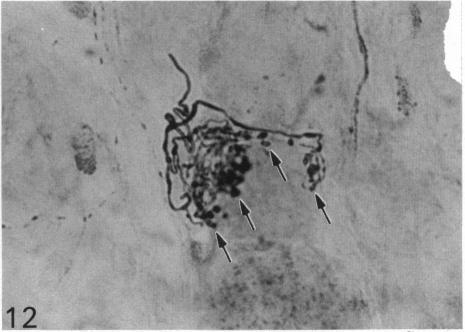

The quantitative cell count showed the presence of about 20,000 ganglion cells with associated satellite elements in the nodose ganglion in the monkey. Among these closely packed cells, at least one-third were substance P (SP) immunoreactive, ranging from faint or moderate to intense staining. Substance P immunoreactivity (SP-IR) was localised in the cell bodies and their long extending neurites. Ultrastructural study showed that SP-IR was not associated with any particular organelles or inclusions. A striking feature of the nodose ganglion was the occurrence of SP-positive pericellular arborisations associated with about 0.5% of the ganglion cells which were almost exclusively SP-negative. The pericellular arborisation displayed diverse morphological forms from a simple tortuous fibre to complex glomerular networks or plexuses encircling the soma of SP-negative ganglion cells. The varicose nerve fibres forming the pericellular arborisations appeared to terminate as 'boutons' contacting the soma of the ganglion cells. Electron microscopic study demonstrated the close spatial relation between the SP-IR profiles and the ganglion cell but there was no direct synaptic contact. In some instances, the SP-IR profiles containing agranular and dense-cored vesicles penetrated the cytoplasm of satellite cells, almost reaching the surface of the soma of the ganglion cell. The sources of origin of the nerve plexuses in the pericellular arborisation were either from the small and sparsely distributed jugular ganglion cells which were intensely SP-IR or from the intrinsic SP-IR nodose ganglion cells. The possibility that the efferent neurons in the dorsal motor nucleus of the vagus could also contribute to the pericellular arborisation was also considered. The function of the pericellular arborisations may be related to the modulation of the SP-deficient ganglion cells with which they associate through the release of SP and probably by way of the satellite cells.

定量细胞计数显示,猴子的结状神经节中存在约20,000个神经节细胞及相关的卫星细胞。在这些紧密排列的细胞中,至少三分之一对P物质(SP)呈免疫反应性,染色强度从微弱、中等至强烈不等。P物质免疫反应性(SP-IR)定位于细胞体及其长延伸的神经突。超微结构研究表明,SP-IR与任何特定的细胞器或内含物无关。结状神经节的一个显著特征是,约0.5%的神经节细胞周围出现SP阳性的树枝状分支,而这些神经节细胞几乎完全为SP阴性。细胞周围的树枝状分支呈现出多种形态,从简单的曲折纤维到复杂的肾小球样网络或围绕SP阴性神经节细胞胞体的丛状结构。形成细胞周围树枝状分支的曲张神经纤维似乎以“终扣”的形式终止于与神经节细胞胞体接触处。电子显微镜研究显示,SP-IR结构与神经节细胞之间存在紧密的空间关系,但没有直接的突触联系。在某些情况下,含有无颗粒和致密核心小泡的SP-IR结构穿透卫星细胞的细胞质,几乎到达神经节细胞胞体表面。细胞周围树枝状分支中的神经丛来源要么是来自强烈SP-IR的小而稀疏分布的颈静脉神经节细胞,要么是来自结状神经节内源性的SP-IR细胞。迷走神经背运动核中的传出神经元也可能参与细胞周围树枝状分支形成的可能性也被考虑在内。细胞周围树枝状分支的功能可能与其通过释放SP并可能通过卫星细胞对与之相关的SP缺乏神经节细胞的调节有关。